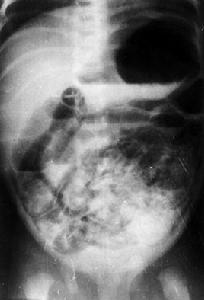

腹部X線平片對本病診斷有重要意義。早期主要表現為麻痹性腸梗阻:小腸排列紊亂,充氣明顯,腸腔內可見多個液平,呈階梯狀。病情進展如腸內氣體進入腸壁則出現腸壁囊樣積氣。腸壁間增寬,腸壁局部出現囊泡狀或串珠狀透亮區,漿膜下積氣時可呈現線,弧狀或環狀透亮區,較重病例因腸內氣體進入門靜脈可見門靜脈充氣征:肝臟可見自肝門向肝內沿門靜脈走行的條型或樹枝狀透亮影,嚴重者可見腸袢固定(腸壞死)氣腹(腸穿孔)、和腹腔積液(腹膜炎)。腸壁囊樣積氣和門靜脈充氣征為本病的特徵性表現。

同時具備以下三項者,即可確診:①全身中毒表現:如體溫不穩、面色蒼白、呼吸不規則和心動過緩等。②胃腸道表現:胃瀦留、嘔吐、肉眼血便、腹脹及腸鳴音消失。③腹部X線表現:腸梗阻和腸壁積氣。